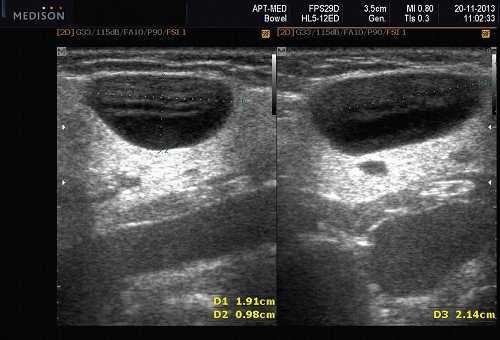

В отечественной и зарубежной литературе встречается много работ, посвященных сиалогии (от греч. Sialon - слюна и logos - учение) - науке о заболеваниях и повреждениях слюнных желез, методах их диагностики и лечения. По данным разных авторов, на долю заболеваний слюнных желез приходится до 24% всей стоматологической патологии. В настоящее время в клинической практике наиболее часто встречаются дистрофические, воспалительные заболевания слюнных желез (сиалоаденозы, сиалоадениты), а также опухоли и врожденные пороки развития слюнных желез. Кроме того, патологические изменения слюнных желез часто сопутствуют другим заболеваниям (сахарный диабет, бронхоэктатическая болезнь, саркоидоз, цирроз печени, гипертриглицеридемия, лимфогранулематоз и др.).

- ультразвуковой метод (является наиболее доступным, безопасным и информативным в процессе дифференциальной диагностики патологического состояния слюнных желез).

- обструктивные сиаладениты, развивающиеся при затруднении оттока слюны при обструкции выводного протока камнем (рис. 5-7) или сгустившимся секретом, а также вследствие рубцового стеноза протока. По распространенности процесса различают очаговый, диффузный сиаладениты и сиалодохит - воспаление выводного протока. Течение процесса может быть острым и хроническим;

Рис. 5. Камень протока поднижнечелюстной слюнной железы.

Рис. 6. Камень в паренхиме поднижнечелюстной слюнной железы.

Рис. 7. Камень в протоке поднижнечелюстной слюнной железы.

Подводя итог, хочется отметить, что ультразвуковое исследование с применением допплерографии во многих наших наблюдениях помогало точно определить характер патологического процесса в СЖ. Однако этот метод диагностики не позволяет однозначно подтвердить или опровергнуть злокачественный характер образования слюнных желез.